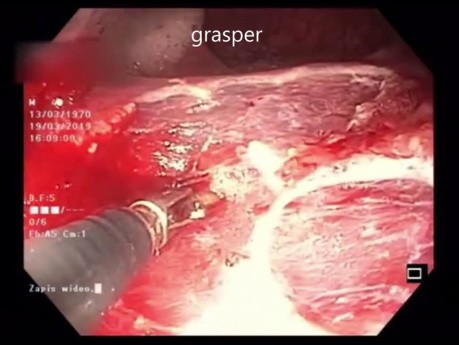

Duża zmiana o morfologii LST -G typu mieszanego...

Duża zmiana o morfologii LST-G typu mieszanego zlokalizowana 40 cm od odbytu na zagięciu z widoczną znaczną ruchomością oddechową. Zabieg rozpocęto od bocznego nacięcia. Następnie kontynuowano mukozektomię...